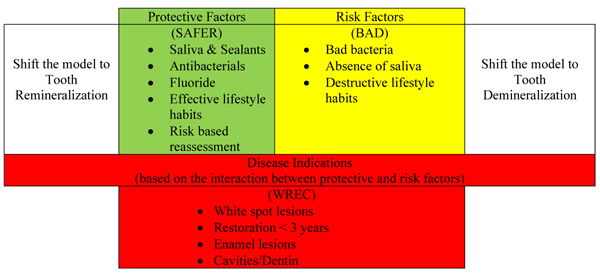

Dental caries is an epidemic and one of the most prevalent and costly diseases due to the increased consumption of sugar [1]. The carious damage of tooth structures depends on sugar consumption, which sometimes causes cavity formation in the three tooth structures: enamel, dentin, and cementum [2]. Young and Featherstone in 2013 stated that caries is a multifactorial disease, and accordingly, they established the caries balance/imbalance model to explain the complex interaction between pathogenic risk factors and protective factors leading to disease indicators (Fig. 1). The model predicts whether the carious lesion can progress, be arrested, or be reversed. For instance, if the protective factors balance the risk factors, the model will shift to a healthy status. On the other hand, if the risk factors outweigh the protective factors, demineralization will start, shifting the model toward caries progression [3]. Fortunately, if this imbalance happens, it can be reversed to avoid surgical treatment of caries, but this should be done before cavitation [4].